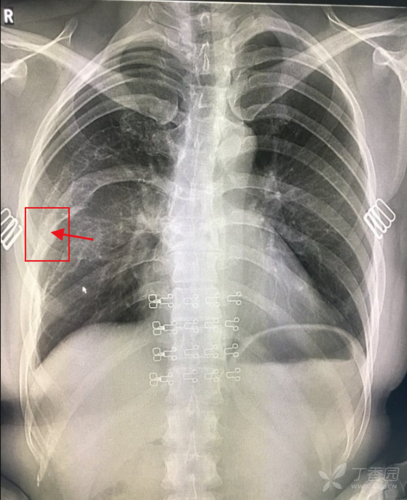

其中右第7肋骨似有骨折后畸形愈合的表现,亦符合骨纤维异常增殖症易伴